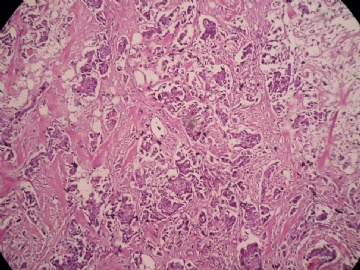

姓    名: ××× 性别:  女 年龄:  45

标本名称:  左侧近乳晕处肿物

简要病史:  患者描述有疼痛

肉眼检查:  肿物一个2.5*2*1厘米,切面灰白质地硬。

• 浸润性导管癌?图2

图2

上皮样细胞,大部分粘附成团成巢,明显浸润。大部分细胞大,核级别高,少数图中见松散的小细胞。未见原位癌。

大细胞考虑浸润性导管癌(3级),小细胞要排除小叶癌。如果有条件请做免疫组化。

Most likely it is INVASIVE DUCTAL CARCINOMA.

DO ER/PR/HER2 STAINS

应该是浸润性导管癌,标本可能有部分自溶现象。